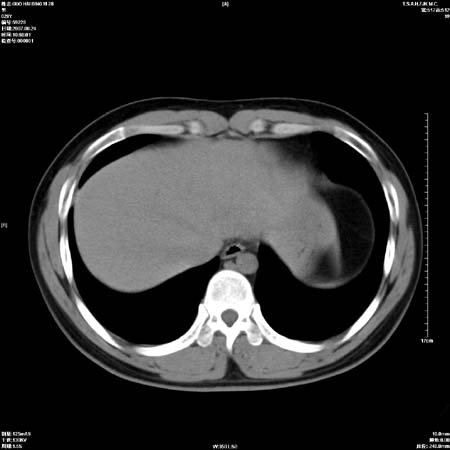

男性,28岁,体检发现左肺病变,患者只有背部隐痛感,哀哉,真不忍心下诊断啊。

左肺门区软组织肿块,左肺上叶支气管开口消失,纵隔内见肿大淋巴结,考虑左中心型肺部,可以做纤支镜取病理确认.

左肺肺门区肿块影,分叶明显,左肺上叶支气管开口受压,纵隔内见肿大淋巴结,考虑左中心型肺癌。

左肺中心型肺癌并纵隔淋巴结转移!考虑为小细胞肺癌,没有手术机会了,只能进行放化了,疗效不错,但极易复发。没办法,现在肿瘤年轻化越来越明显了。